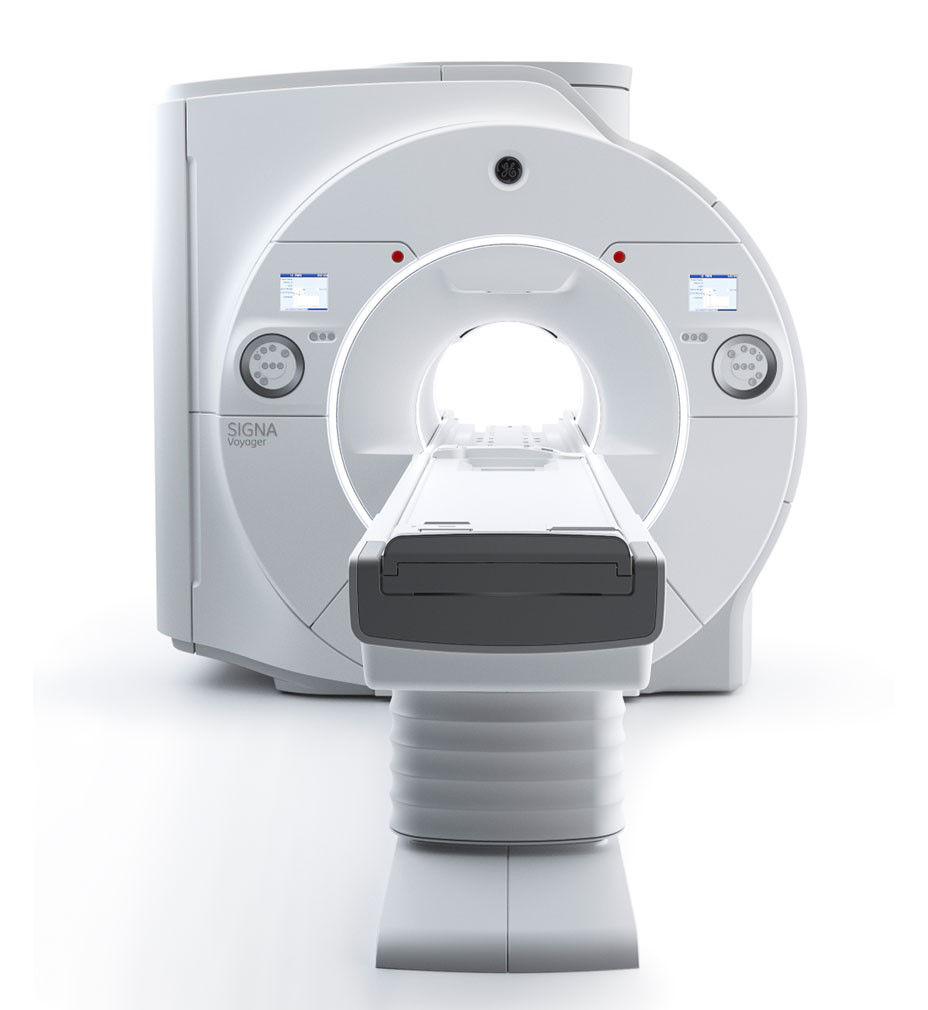

SIGNA™ Voyager 1.5T wide bore MRI scanner

Exceptional imaging in a compact 1.5T wide bore, MRI scanner

SIGNA™ Voyager gives technologists and radiologists quick, patient-friendly exams with consistent, optimal image quality. This intelligent 1.5T wide bore MRI scanner is designed to be a masterful balance of comfort and productivity, with features that improve the patient experience and software that can optimize image quality and reduce exam time.

Multiply the value of advanced 1.5T imaging in a smaller, more efficient MRI with SIGNA™ Voyager. With patient-friendly AIR™ Coils that maximize comfort and intelligent Workflow Solutions that reduce exam time, this wide-bore system makes use of UHE technology and Total Digital Imaging to consistently deliver premium imaging performance with a low-running cost.